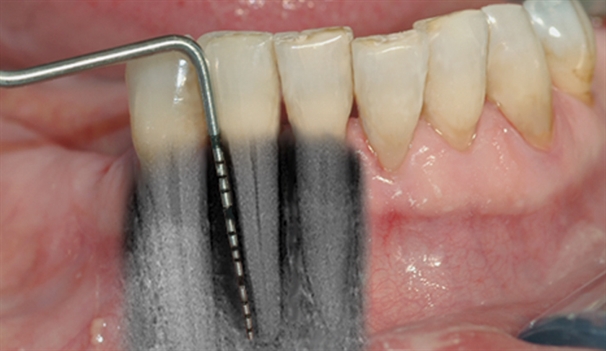

• perio stor 3

perio stor 3

Instrumentet er her lagt utenfor tannkjøttet for å vise hvor stort festetapet egentlig er.